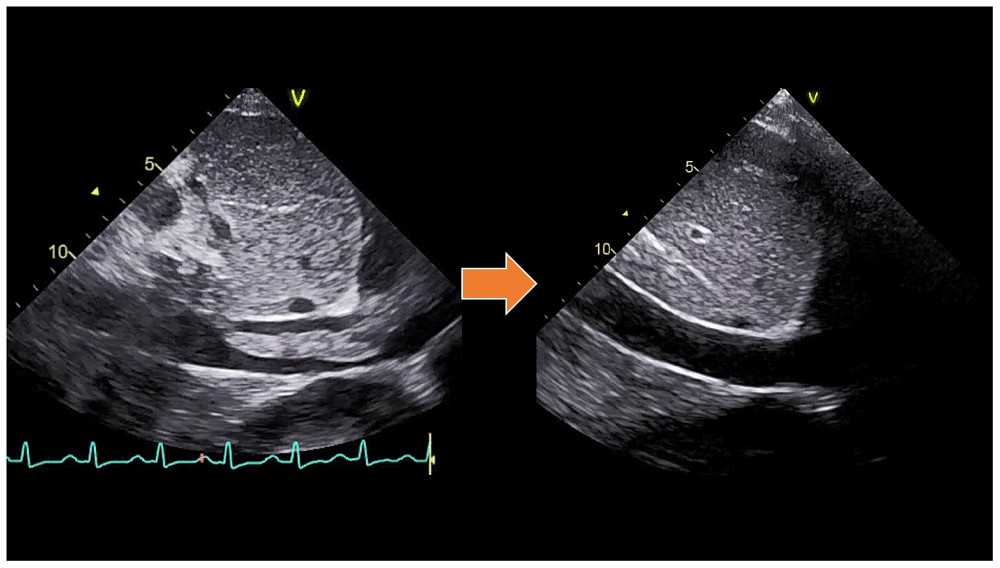

A chest CT scan (Figure 5) showed right pulmonary artery embolism at ± 5.9 cm from bifurcation on the anterior side of the intermediate right bronchus; emboli on the left pulmonary artery bifurcation and the left pulmonary artery basal part; multiple right intraatrial hypodense lesions not showing contrast enhancement leading to a visualization of the right intraatrial thrombus; pulmonary infarction in the lateral-posterior segment of the base of the inferior lobe of the right lung, the lateral-posterior segment of the base of the inferior lobe of the left lung, and the anterior segment of the superior lobe of the left lung; and superior vena cava thrombus at VTH level 1-5. Figure 6 shows the protruded thrombus in the right atrium passing through the tricuspid valve. TTE also showed the position of the thrombus moving from the inferior vena ca va towards the right atrium (Figure 7). The movement of the large protruding thrombus can be seen in supplementary video files 1–35–7.

In the CVCU, we gave the patient hemodynamic support with Norepinephrine starting at 50 nanograms/kg/minute by titration. Reperfusion was carried out by giving a loading dose of 250,000 units of Streptokinase intravenously for 30 minutes, followed by 100,000 units of Streptokinase per hour for 24 hours with intravenous continuous pump. After revascularization, the patient's hemodynamic condition improved until vasopressors/inotropic drugs could be tapered off. TTE also showed the disappearance of the large protruding thrombus (supplementary video files 4–5)8,9. After the patient’s condition was stable, he was transferred to the cardiology ward until the patient was discharged after one week of thrombolytic treatment. In his discharge, rivaroxaban was prescribed at a daily dose of 20 mg as an oral anticoagulant for at least three months. The diabetes mellitus was well-controled with subcutaneous injection of 6 units insulin aspart three times daily before meals.